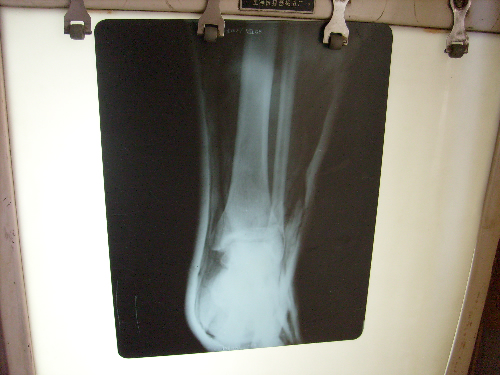

治愈前

姓名: 孟菊英 女 36岁 龙口市洼里煤矿,右踝关节腓骨头骨折,合并距骨错位。